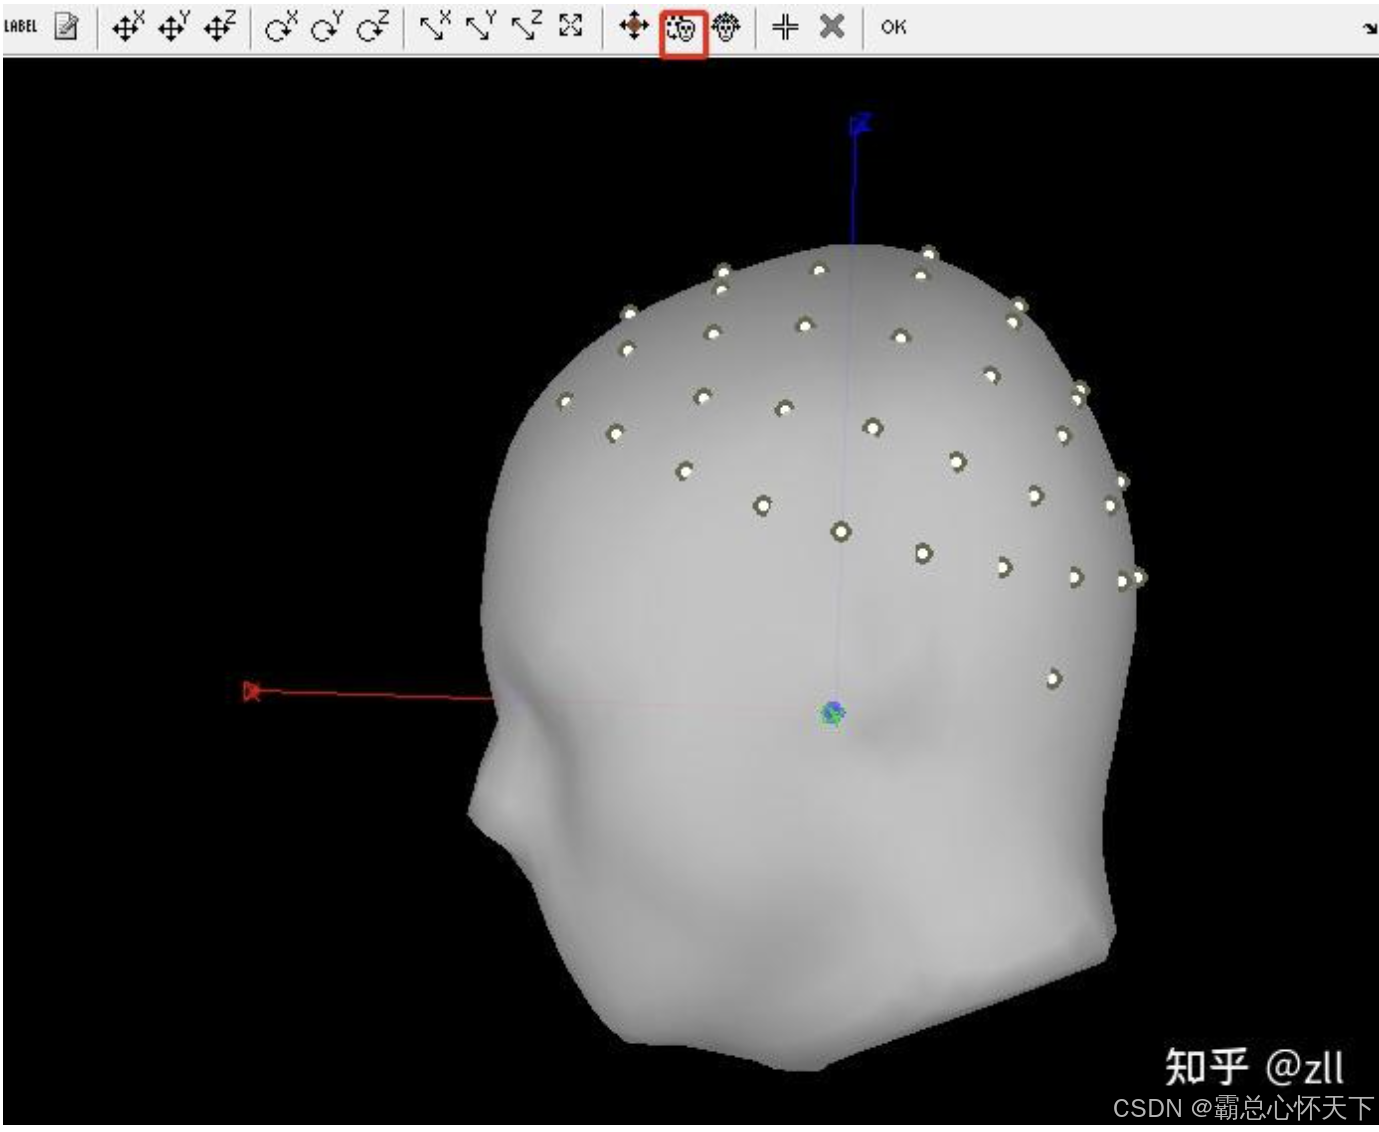

后会打开一个显示通道的页面

最上面一行的菜单,可以停留在图标上,会出现英文解释,自己看英文释义。根据上下左右前后移动外面的那个大黄罩子(大黄罩子相当于所有的通道点连接起来的曲面)

更改之后,不要忘记电极最上面那行图标中的OK,还可以查看电极位置,操作如下

这里是MEG和EEG另一个区别,这个区别也是我花了很长时间才搞清楚的。。。

因为EEG的电极都是贴合头皮的,所以正常EEG最后的电极显示图应该是类似于这样的,

但是MEG不一样,它的通道就是要悬浮着的,后来我去查了MEG的采集操作图片,确实,通道是不贴脑袋的

假如我这里理解的有误的话,请大家积极指正,以免误人子弟,目前为止我还是这样认为的